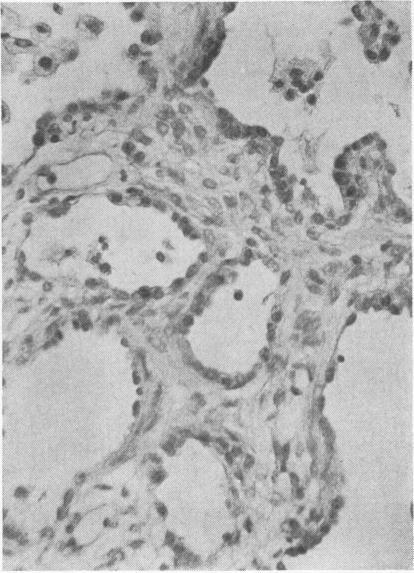

The effect of oxygen on the lung.

J Clin Pathol Suppl (R Coll Pathol). 1975;9:75-80.